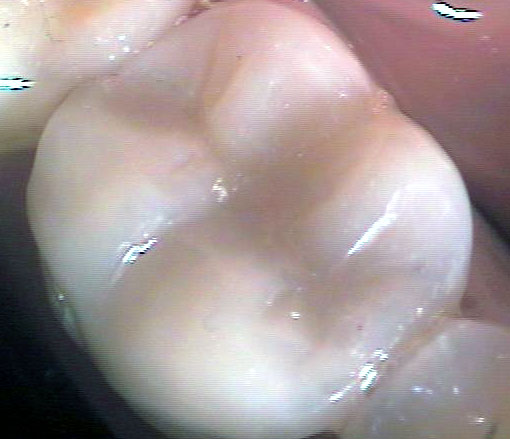

Композитните индиректни възстановявания (т. нар. вставки) са добро решение за възстановяване на кариозни дефекти с по-голям обем. Терминът вставка има руски произход - води началото си от глагола вставлять, който означава поставям. Тъй като през 60-те и 70-те години на ХХ век са се изработвали доста метални вставки, а тогава рускоезичната литература е била най-широко разпространена, е разбираемо защо терминът вставка се използва в българската дентална медицина и до днес. На снимката горе са показани две композитни вставки на зъби 46 и 47. При двата зъба остатъчните странични зъбни стени са били твърде изтънели, което е принудило лекуващия дентален лекар да ги намали на височина. Това се прави с цел вставката да покрие зъба и да го предпази от бъдещо фрактуриране. В този случай цялата дъвкателна повърхност на зъба е изградена от композитен материал.